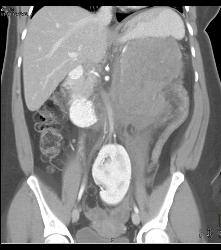

Glomus Tumor